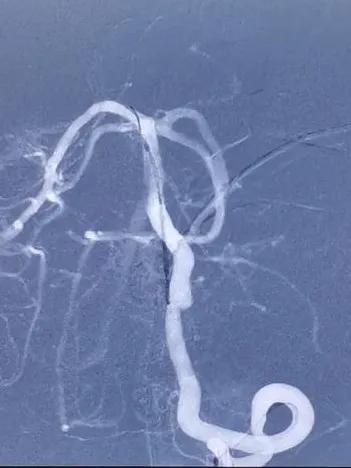

静脉肝素化,T-track支架导管微导丝导引下超选跨病变部位置入右侧大脑后动脉段。予以4.0×25mm Tubridge®血管重建装置于左椎动脉脊髓前动脉开口处近侧锚定缓慢释放,支架打开良好,贴壁完全。

支架置入过程